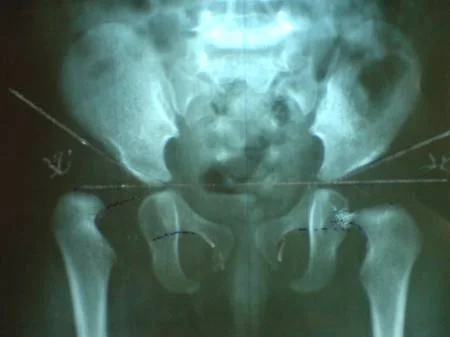

Las Radiografías tienen su indicación después de los tres meses de edad, el estudio se basa en dos proyecciones, la primera con las piernas en posición neutra y las rotulas al cenit, y la segunda con proyección de Von Rosen, la cual consiste en colocar la articulación coxo femoral en abducción de 45º, extensión plena y rotación interna.

En el estudio radiológico trazamos la línea de Hilgenreiner que pasa a través de ambos cartílagos trirradiados, el arco de Shentón es el arco formado al trazar una línea siguiendo la parte inferior del cuello del fémur (calcar) y la parte inferior de la rama iliopubiana, si el arco no es continuo traduce un ascenso de la cabeza femoral, la línea de Perkins es perpendicular al borde externo del acetábulo, el índice acetabular es el ángulo formado entre una línea trazada a lo largo del techo acetabular y la línea de Hilgenreiner.

De la intersección de las líneas de Hilgenreiner y la de Perkins surgen los cuatro cuadrantes de Ombrédane, en donde en una cadera normal el núcleo epifisiario de be ubicarse en el cuadrante infero interno, y en la cadera luxada el núcleo se desplaza al cuadrante supero externo.

Cuando no contamos con el recurso del ultrasonido, la clasificación radiológica descrita por Tönnis (1982,1987), nos permite clasificar la displasia evolutiva de la cadera en cuatro tipos, dependiendo de la posición del centro del núcleo de osificación femoral en la radiografía AP de cadera.

· Grado I: el centro de osificación es medial a la línea vertical que pasa por el borde superior del acetábulo (cadera normal).

· Grado II: este es lateral a la línea de Perkins, pero debajo del borde superior del acetábulo.

· Grado III: el centro de osificación está a nivel del borde acetabular.

· Grado IV: centro de osificación por encima del borde acetabular.